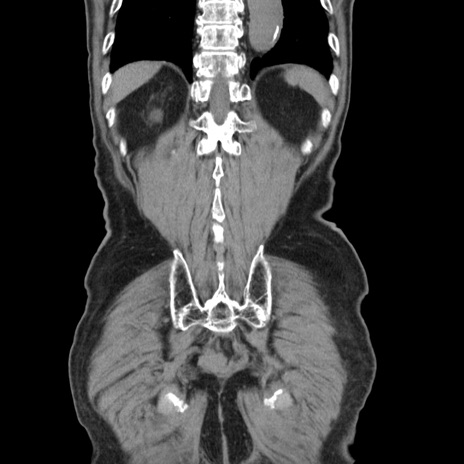

症例24(冠状断像)

【症例】80歳代男性

【主訴】左側腹部痛、嘔吐

【現病歴】本日早朝より左腹部に痛みあり。昼頃嘔吐認めたため、救急要請。

【既往歴】直腸癌(Mile手術)、胆摘

【身体所見】意識清明、BT 35.9℃、BP 221/93mmHg、SpO2 97%(RA) 、腹部:左ストーマ周囲に限局性の腹部膨隆あり。 膨隆部自発痛・圧痛あり・軟。

【データ】WBC 7700、CRP 0.09